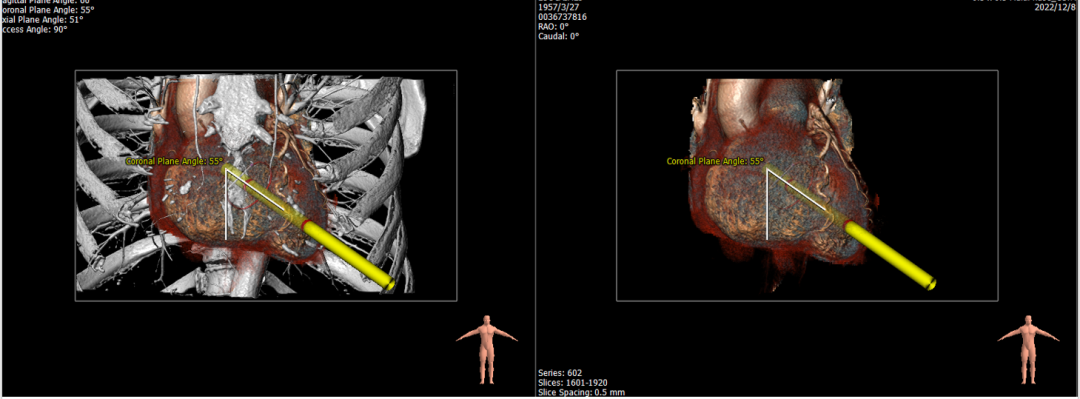

经华西医院心外科MDT团队综合评估,该患者为老年重度FMR患者,考虑外科瓣膜置换手术风险极高,决定进行MitraFix®经心尖二尖瓣植入。术前心脏CTA瓣环面积折算最大直径37 mm 模拟植入34号二尖瓣瓣膜, 收缩末心室Neo LVOT面积约230mm²。

术前心尖入路评估

手术采用左侧第六肋间微创5cm切口心尖入路,在超声引导下,清晰识别MitraFix®输送系统准确跨瓣,并将人工瓣膜准确释放于二尖瓣瓣环,瓣膜释放后支架贴合牢固,术后无反流,二尖瓣前向血流通畅、跨瓣压差3mmHg,左心室流出道通畅,流出道血流速度为1.0m/s. 后顺利撤出输送系统,关闭心尖切口,手术顺利结束。